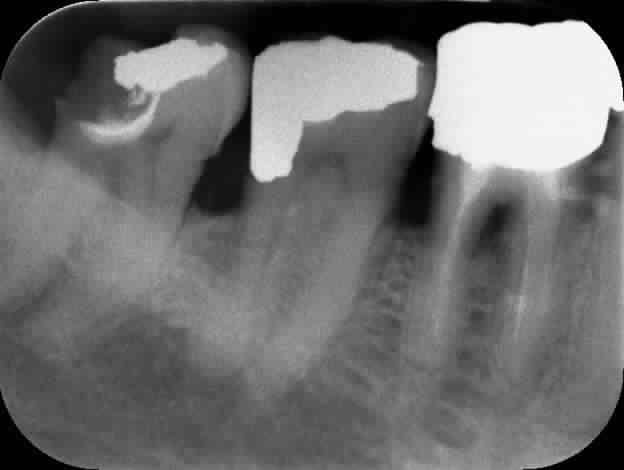

Petit cas clinico-commercial (la radio est du 14.6.2012).

14.6.2012 Je vois en consultation le patient, devinez pourquoi?... L'amalgame sur 48 est pété... (voir la radio) (la 18 est présente et intacte).

(La radio est pourrie, je n'arrive pas à la publier en TIFF, désolé)

En urgence, je mets un IRM si pas de douleurs, et ouverture si douleurs. Par la suite, endo sur la 8, TFM et dent pro, le temps de faire un assainissement paro global. Je reprendrais aussi la 6, qui n'est pas nette à tous points de vue.

Retraité aisé, vient à l'heure, n'a jamais raté de rdv, supporte très bien les radio (une plaque de Digora aussi loin dans la bouche, t'essaiera ;-) ) (la radio n'est pas floue mais dégradée par la compression).